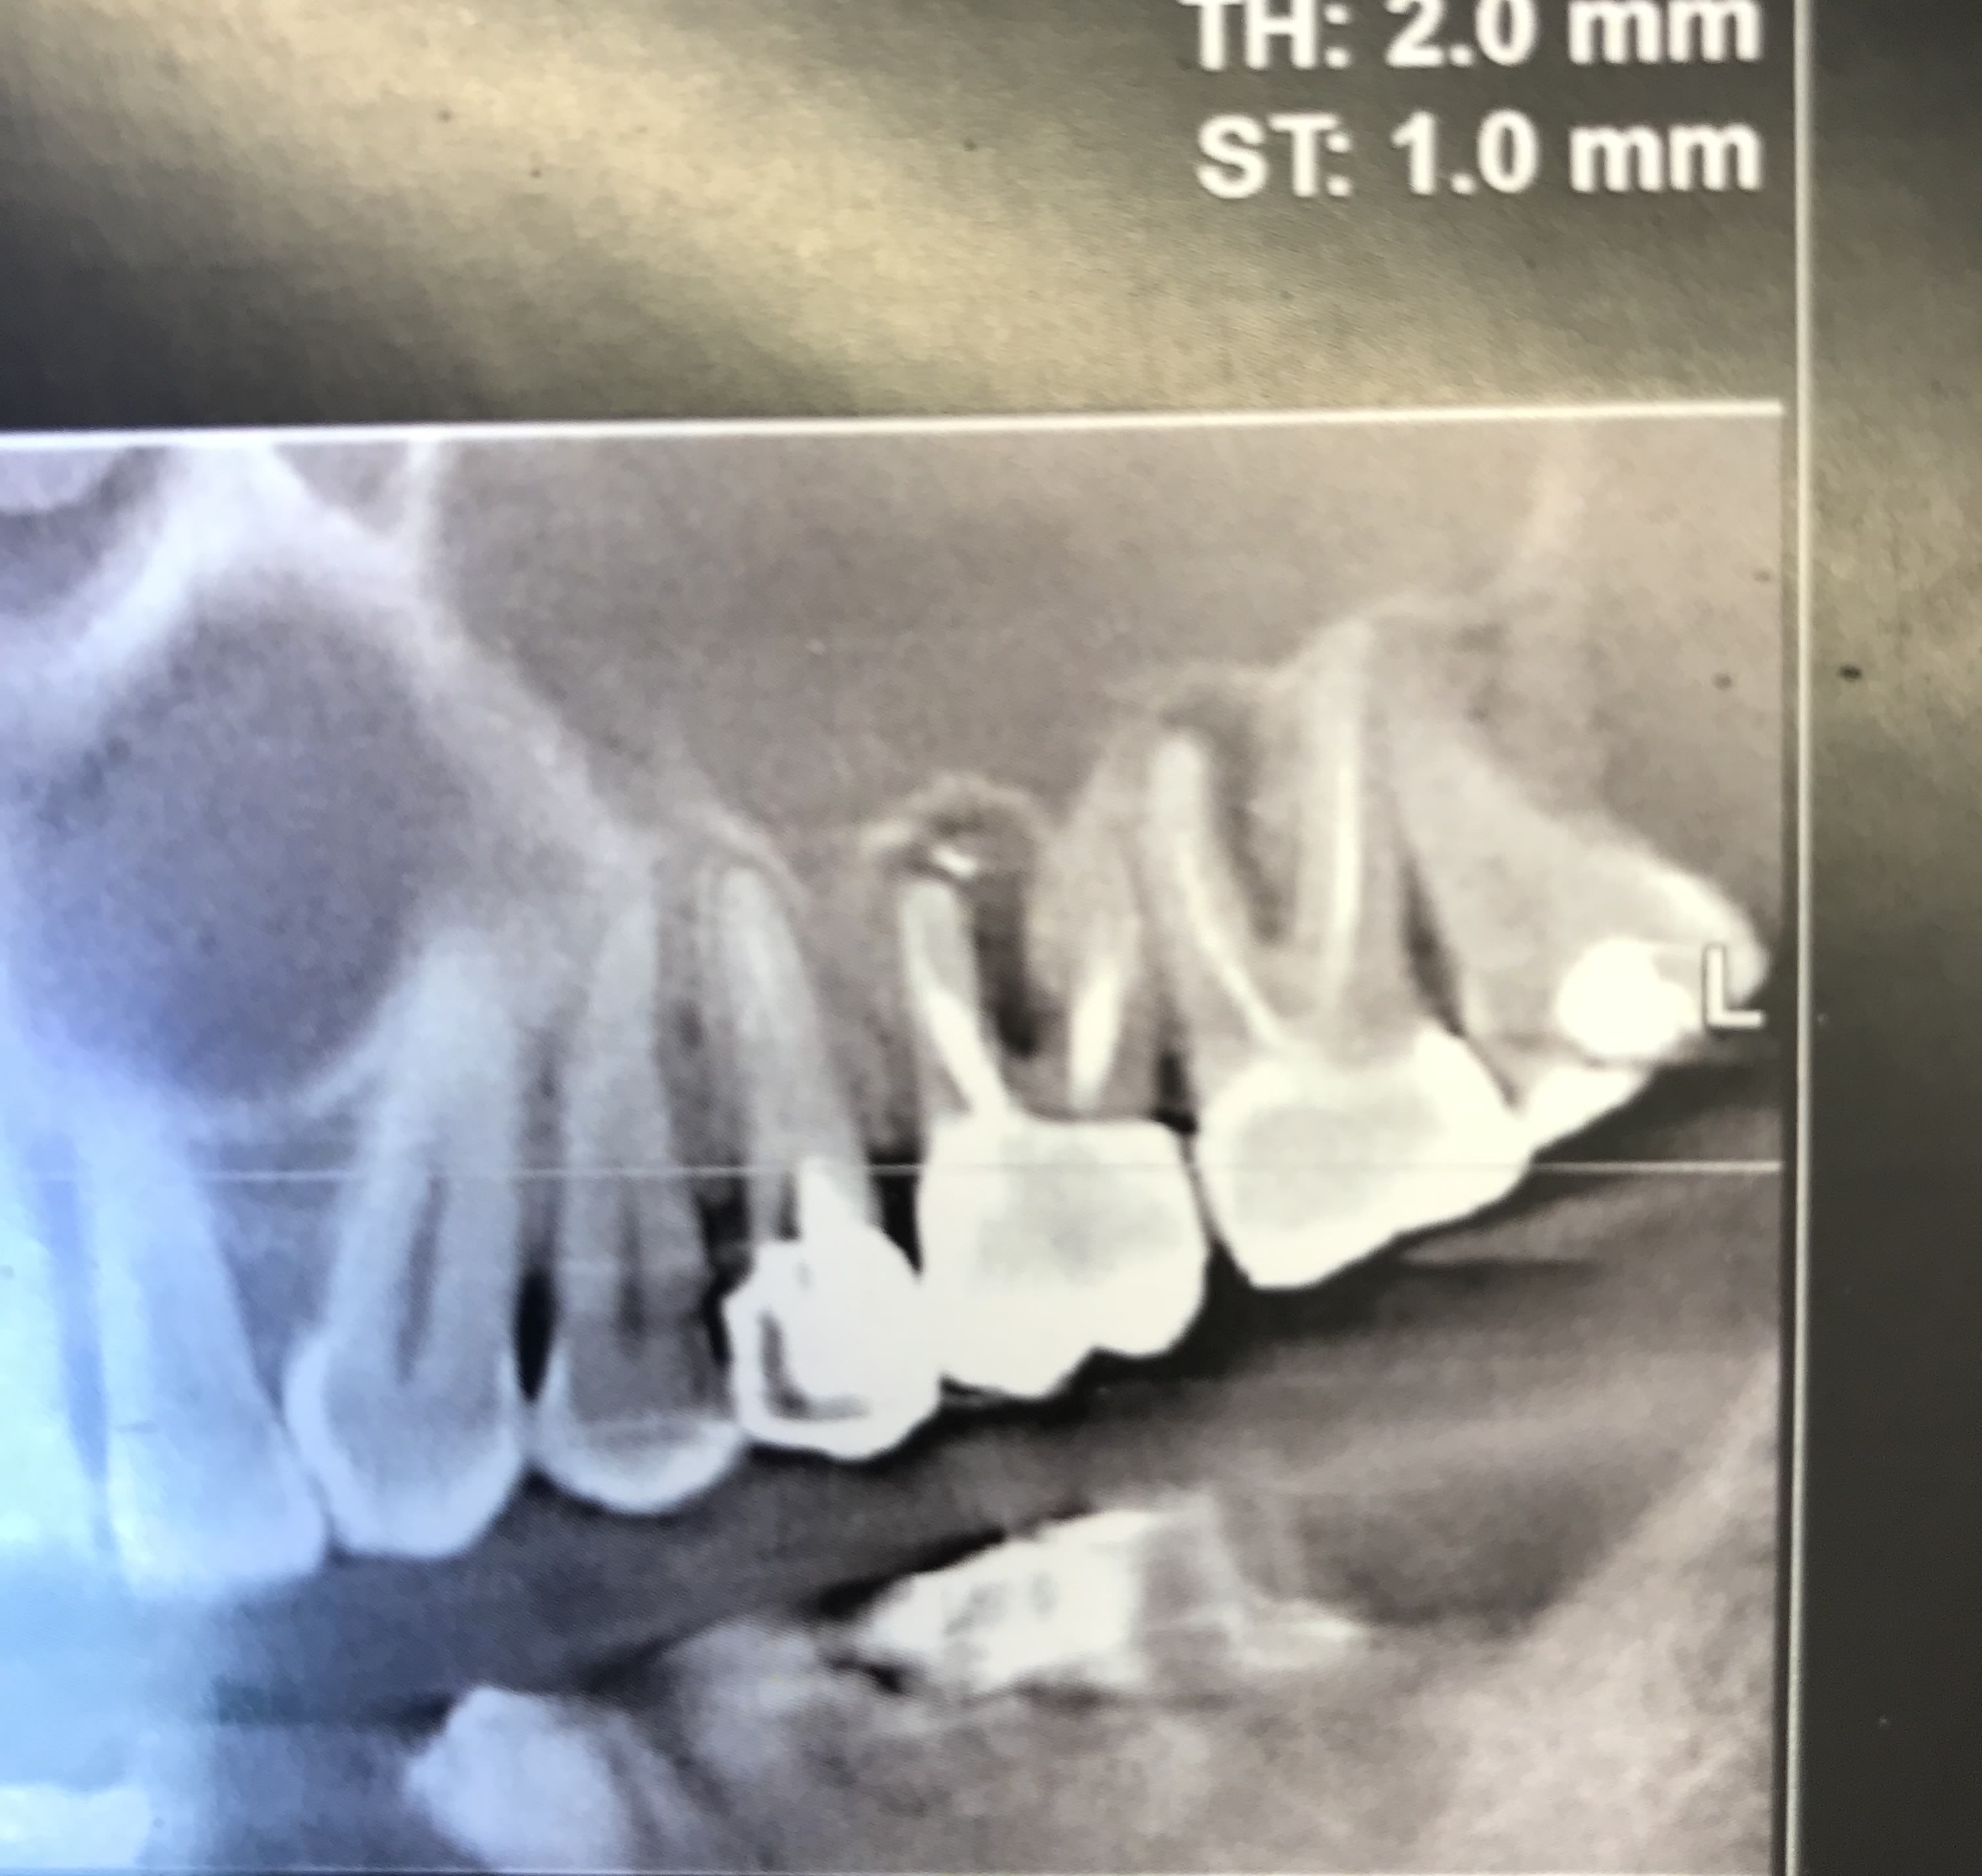

Tiens ... patient qui vient en urgence pour sa 26 douleur +++. Pas le temps d’extraire. Atb.

Entre temps il me ramène son scanner car je dois lui poser des implants secteur droit. Je regarde : merde y a une lésion sur la 27 aussi.

- du coup j’extrais la 26 et en même temps j’en profite pour faire une ERI sur 27